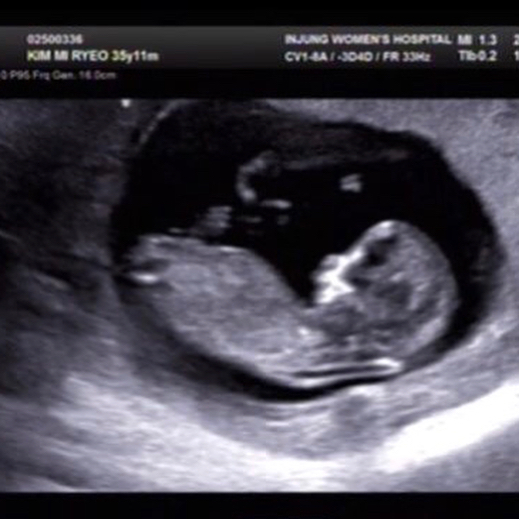

4일 김미려는 자신의 인스타그램에 "모아 동생 모둥이. 곧 4개월. 둘째는 이름을 뭘로 할까나. 엄청 활발한 아이인 듯. 체력을 키워야겠다"라는 글과 함께 태아 초음파 사진을 게재했다.